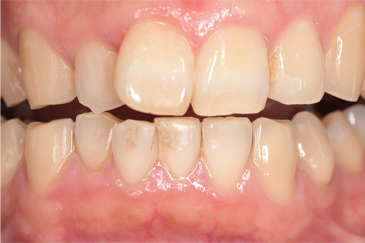

CASE 3

Before

After

基本情報

| 年齢・性別 | 30代・女性 |

| 主訴 | 定期検診 |

| 治療内容 | PMTC |

| 治療期間 | 60分 |

| 治療費 | 5,750円 |

| リスク・副作用 | しみる可能性があります。 |

| 治療方針 | PMTCでステインの除去。 |

| 担当者所見 | ステインが付きやすいため、3カ月毎の定期検診で除去する。 |